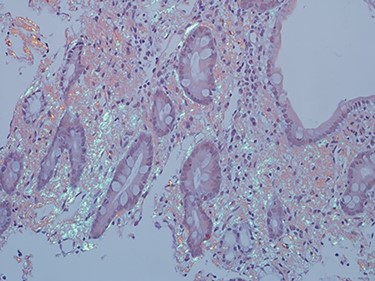

As work up for his abdominal pain and anemia he underwent gastroscopy on 29 October 2020 that revealed congested and nodular gastric mucosa (mass-like) and at lesser extend in the first and second part of duodenum (Figs 1 and 2). Biopsies were taken from the gastric lesion and duodenum. Histopathological findings from gastric mass and duodenum showed marked stromal hyalinosis, which appeared as a cellular pink material on H&E stain (Figs 3 and 5). Congo red stain (amyloid stain) showed apple green birefringence under polarized light on both gastric and duodenal biopsies (Figs 4 and 6).

Amyloid stain (Congo red) on duodenal biopsy showing the classic apple green birefringence under polarized light.